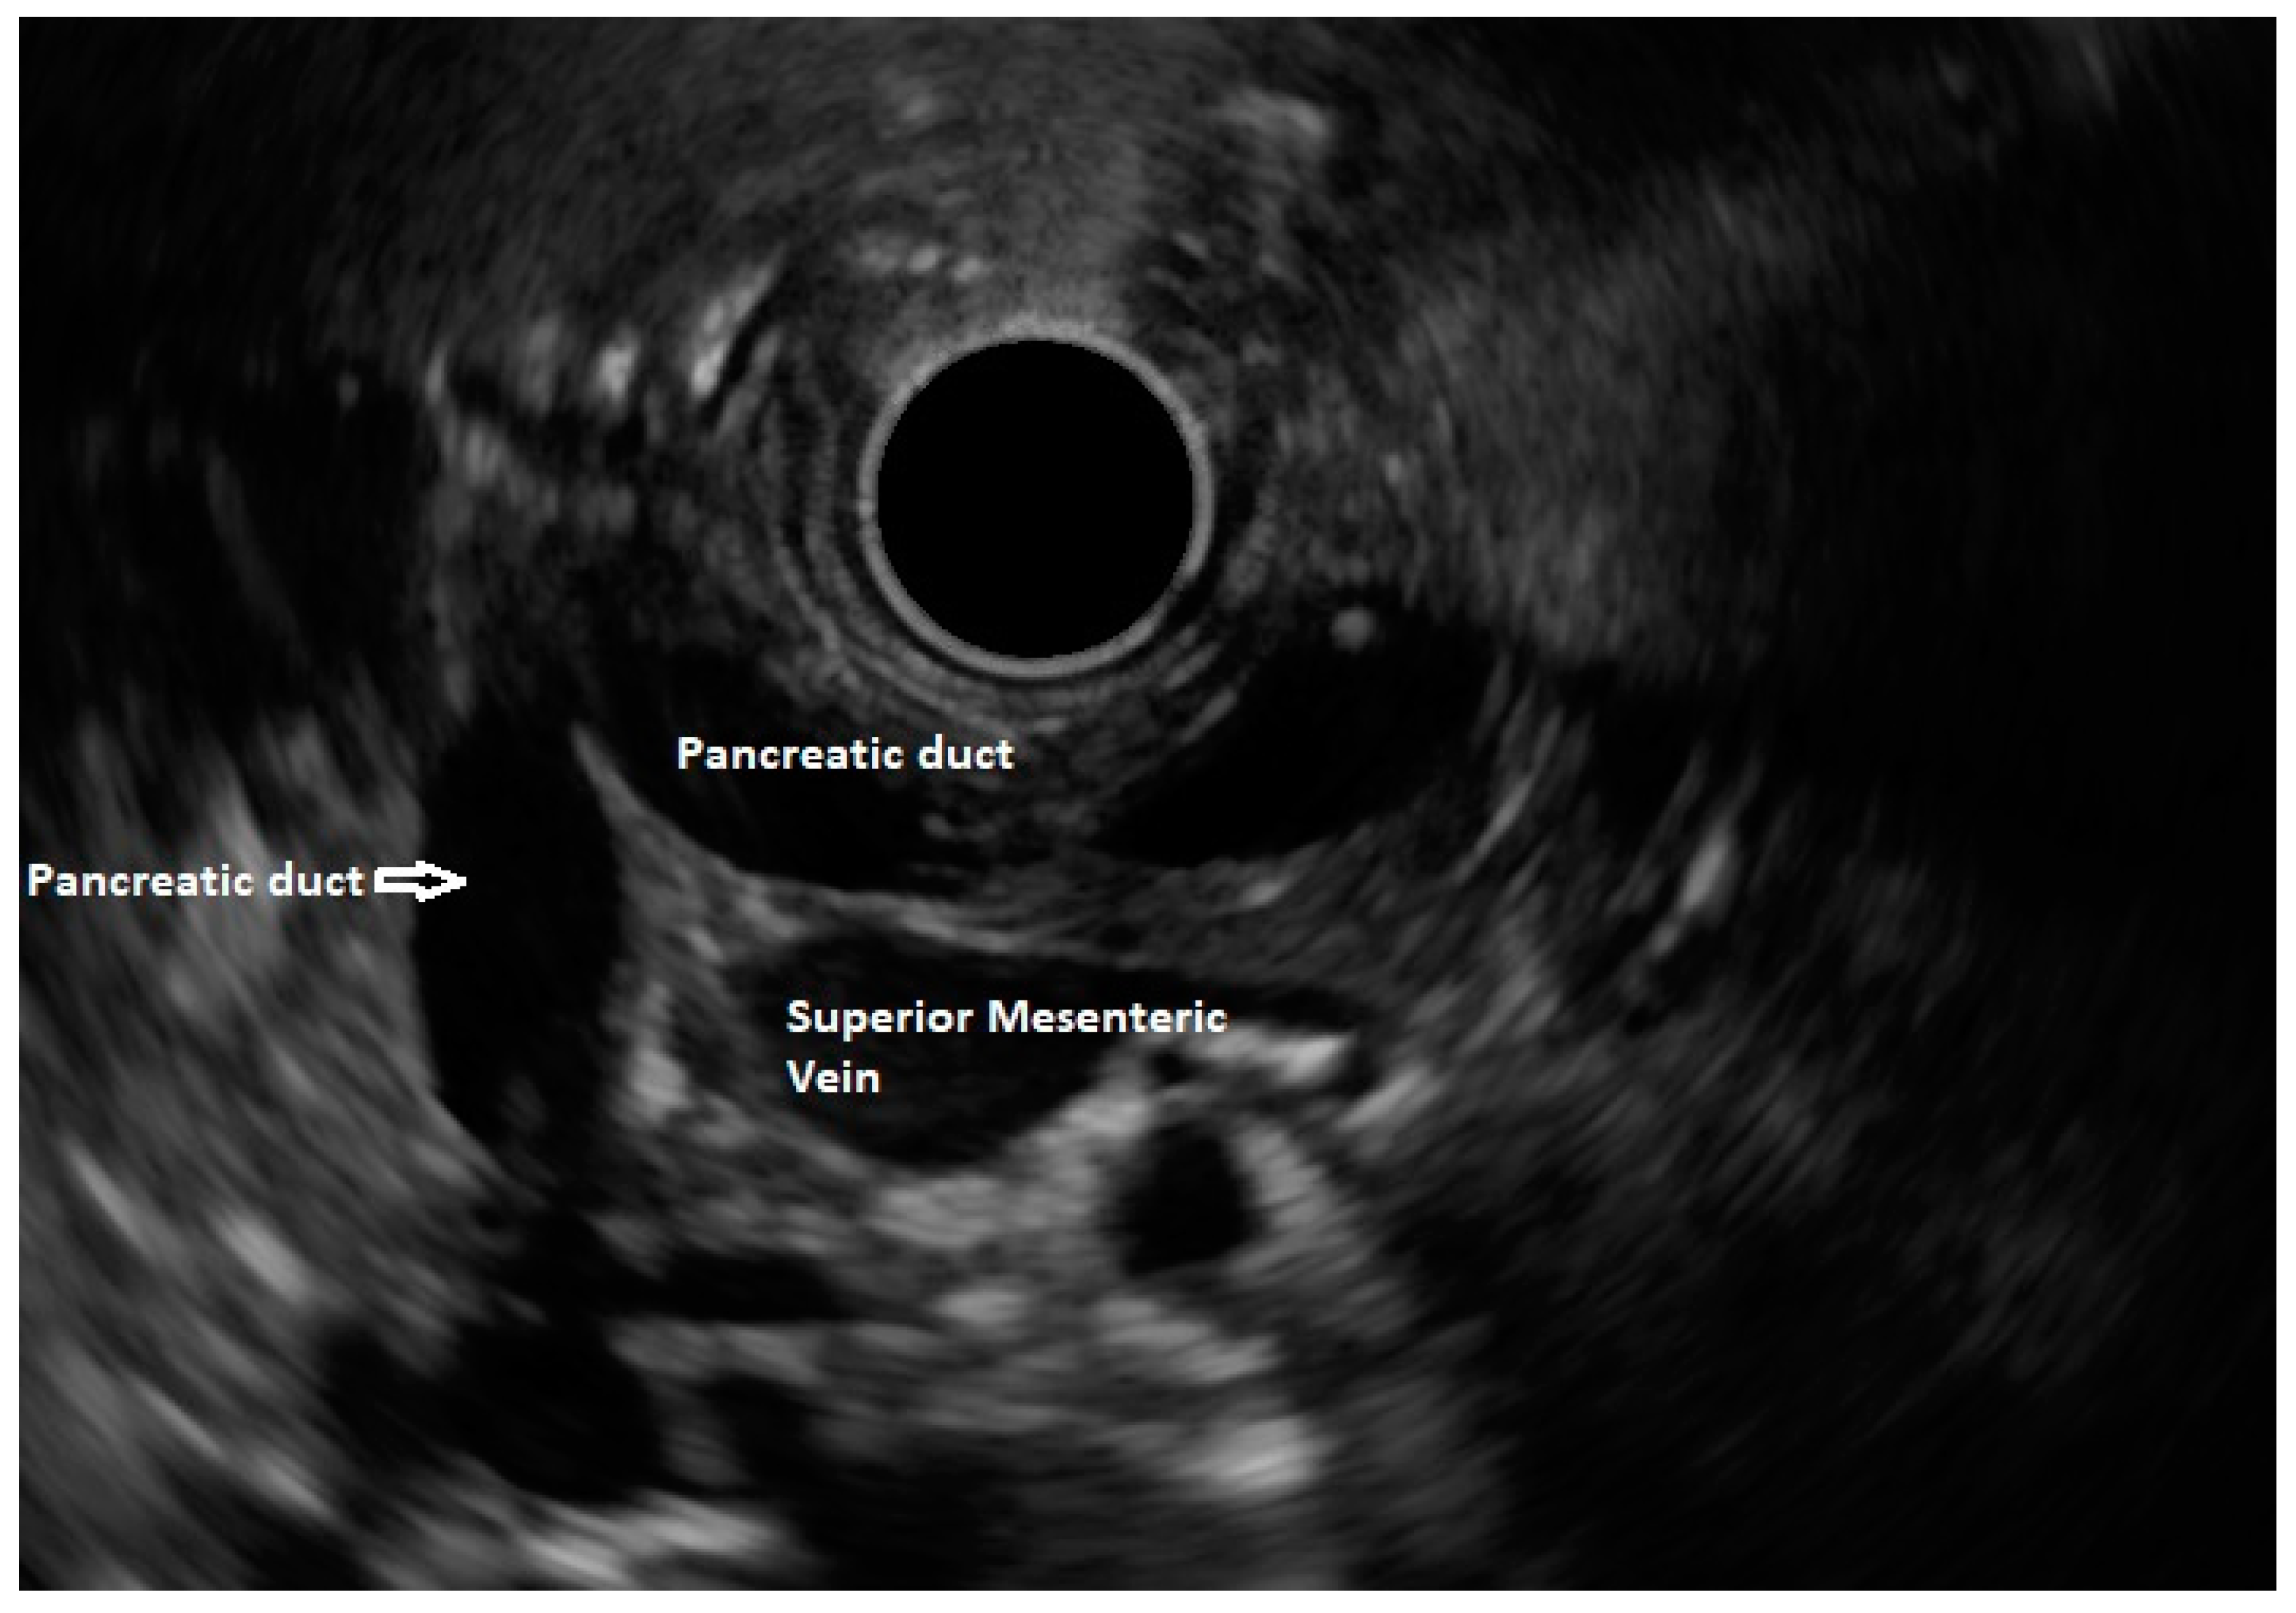

In routine endosonographic examination, all parts of the pancreas are comprehensively examined when seen from three stations, that are the apex of the duodenal bulb, papilla and distal to the papilla. Among these, the best position is the apex of the duodenal bulb as it brings the major portion of the head of pancreas, distal common bile duct and the portal vein in the same frame. For positioning, the EUS scope is advanced along the greater curvature of the stomach and when pylorus is visible, the tip of the scope is negotiated through it followed by air insufflation of the duodenal bulb. This is followed by gentle downward deflection of the tip of the scope making the duodenal bulb visible. Doppler imaging helps differentiating bile duct from the arteries (hepatic artery and the gastroduodenal artery) and portal vein. At this point, the endosonologist gets the view of distal CBD, pancreatic duct, and the portal vein in a single frame in which one structure appears to lie on top of the other and this is called as the ‘stack sign’ (Figure 1) and absence of stack sign suggests possibility of pancreas divisum (Figure 2). As these structures do not lie in the same plane, various manoeuvres like clockwise and counter clockwise rotation and right and left torque are required for a detailed examination of these structures.12 Although this sign is conventionally described in radial EUS, linear EUS can also detect similar anatomical configuration although there are some subtle differences in linear EUS. In linear EUS, usually the ‘stack’ consists of distal CBD and pancreatic duct which are seen on parallel axis (portal vein is not seen). However, superior mesenteric vein (SMV) or artery (SMA) can be seen on linear EUS in a different axis once a clockwise rotation is performed and origin of portal vein from the SMV can also be easily demonstrated (Figure 3).27

Figure 1. Radial EUS showing both ventral pancreatic duct and common bile duct stacked together. This finding rules out pancreas divisum.